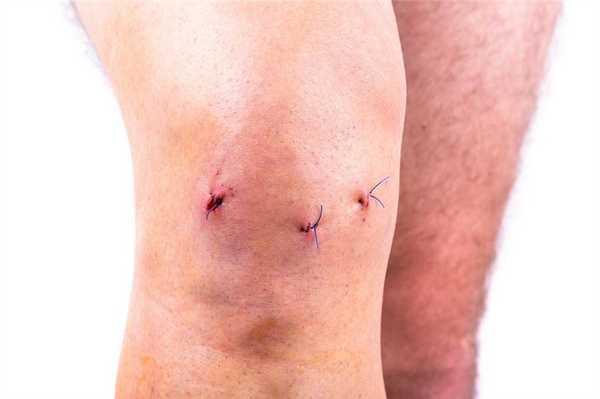

Бережное отношение к послеоперационной ране. Вдоль Вашей раны по передней поверхности области коленного сустава будут наложены швы или специальные скобки или же она будет ушита подкожным швом. Скобки или швы будут сняты примерно через две недели после операции. Подкожный шов не требует удаления.

Предосторожности при уходе за послеоперационной раной

Из-за риска инфицирования первые две недели послеоперационную рану нельзя мочить проточной водой. Поэтому мыться следует с особой осторожностью, а ванны и душа лучше вовсе избегать. Во время мытья необходимо следить за тем, чтобы повязка не намокла. Если же это случилось, то ее следует заменить. В противном случае повысится риск нагноения послеоперационной раны.

Пока послеоперационный рубец не заживет, его нельзя тереть мочалкой. Ведь кожа там очень тонкая и нежная, а травмировать ее крайне легко. Ухаживать за швом после операции следует согласно рекомендациям специалиста.